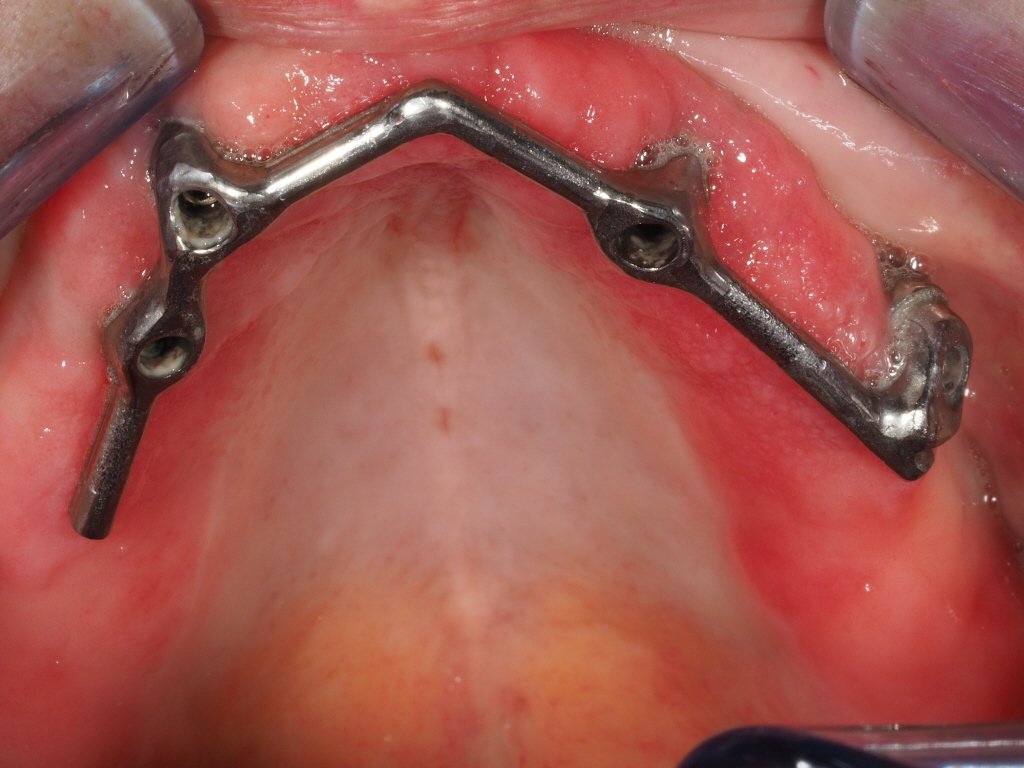

Acude paciente a nuestra clínica para ver si la podemos ayudar. No se sujetan bien las prótesis que lleva. La Clinica dónde le colocaron los implantes ha desaparecido. Necesitamos saber [...]

buenas tardes compañeros, me podriaid ayudar con la marca de estos implantes? muchas gracias por vuestra atencion, 1 saludo

Podéis identificar estos implantes?, conexión interna con un hexágono y luego otro hexágono más profundo con lóbulos, tornillo interno de métrica 1,8